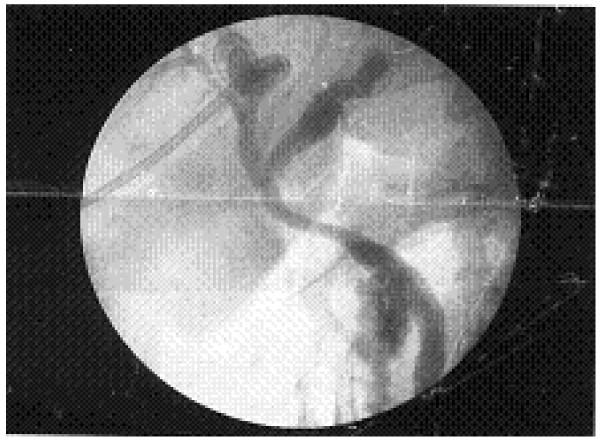

We present the case of a 44-year-old Asian man with Mirizzi's syndrome who was initially diagnosed as having cholangiocarcinoma based on his clinical presentation, raised cancer antigen 19-9 levels and radiological findings. Our patient was diagnosed as having Mirizzi's syndrome intra-operatively and subsequently a cholecystectomy was performed with restoration of biliary drainage. Careful clinical assessment during surgery with the help of intra-operative frozen section helped in establishing the definitive diagnosis and altered the surgical procedure for our patient.

我们报告一例44岁亚洲男性Mirizzi综合征病例,该患者最初根据临床表现、癌胚抗原19-9水平升高及影像学检查结果被诊断为胆管癌。我们的患者在术中被诊断为Mirizzi综合征,随后进行了胆囊切除术并恢复了胆汁引流。术中借助冰冻切片进行仔细的临床评估有助于明确诊断,并改变了我们患者的手术方式。